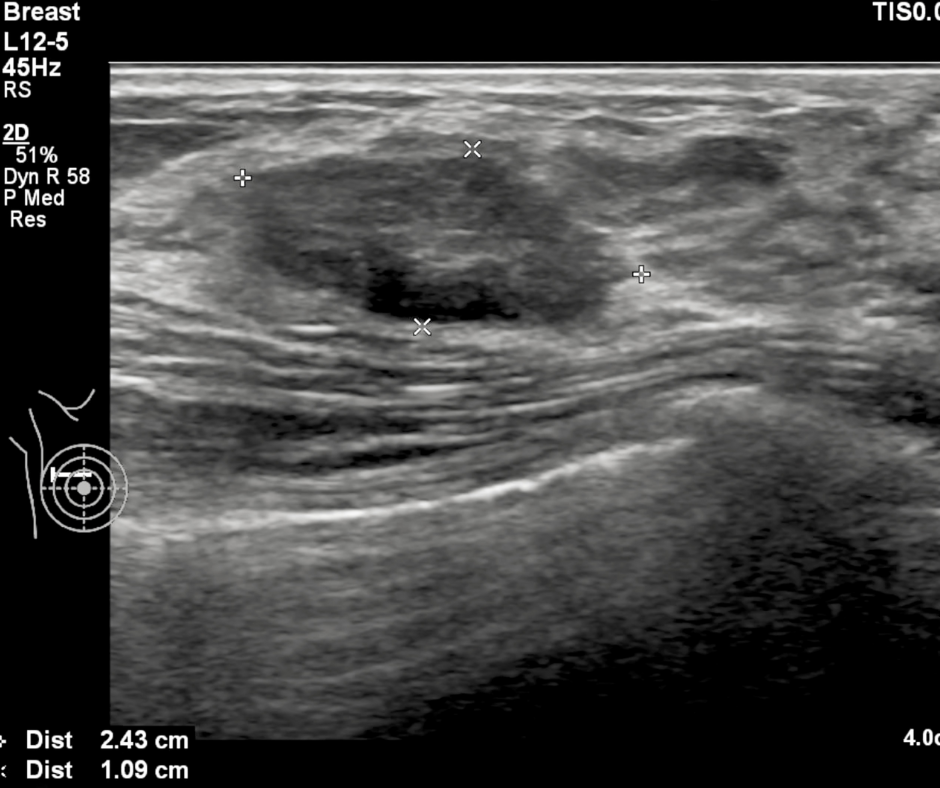

Researchers found that ChatGPT offered appropriate responses to 22 out of 25 patient-oriented questions on mammography screening, dense breasts, BI-RADS scoring and other topics related to breast cancer screening and prevention.